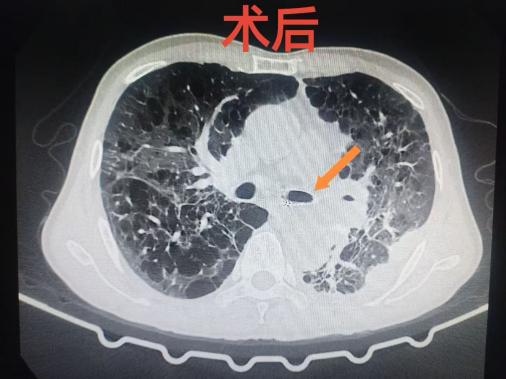

术中,手术团队先置入硬质支气管镜,在确保患者持续通气安全的前提下,再联合软质支气管镜精准定位,成功在堵塞的左主支气管内放置了一枚支架,瞬间打开了“生命通道”。术后,患者呼吸困难立即缓解,缺氧状况显著改善,左肺重新复张,第二天便转回普通病房,为后续抗肿瘤治疗赢得了宝贵时机。